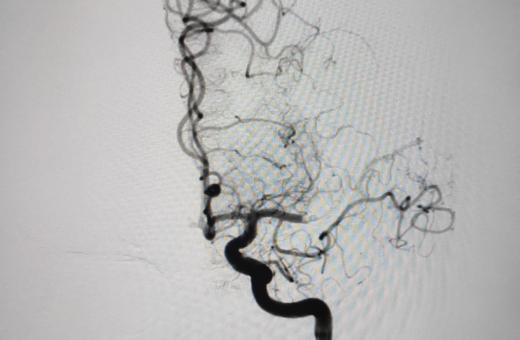

21/02/2020 El Trueta comença a implantar vàlvules aòrtiques transcatèter per tractar sense cirurgia pacients amb estenosi aòrtica